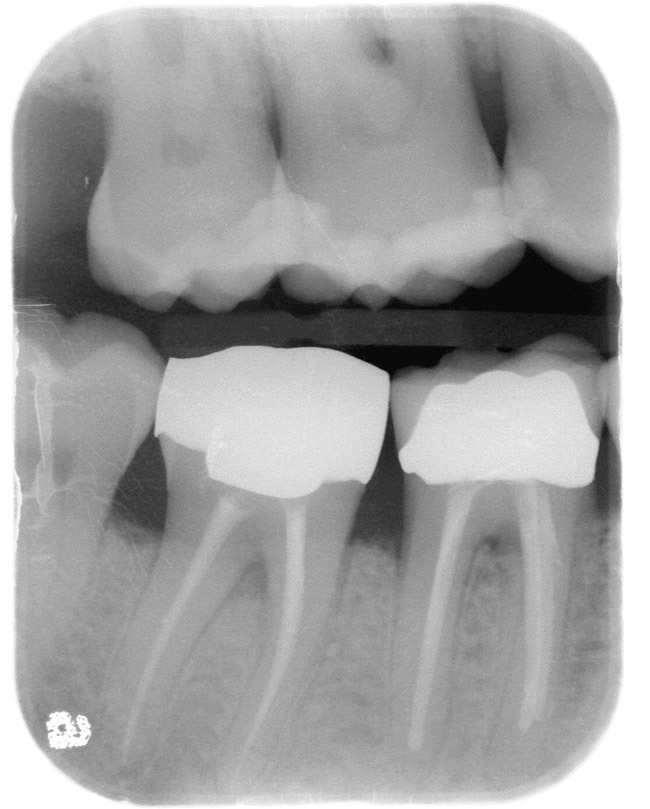

Figure 3  EVALUATION PARAMETERS  The Rule of Thirds: The canal or canal space preparation should not be any wider than one third the mesiodistal root diameter after the endodontic access.

Figure 3

If the tooth has been endodontically treated, the remaining tooth structure relative to the post space needs to be evaluated. The Rule of Thirds is used in this situation. It states that the canal or canal space preparation should not be any wider than one third the mesiodistal root diameter after the endodontic access (Figure 3).3 Once the clinician determines whether adequate tooth structure is present, the second area to evaluate is the distance of the fracture/caries from the crest of bone. To avoid biological width impingement, the minimum distance needed from the osseous crest to the final margin placement is 2.5 mm (Figure 4). As determined in cadaver studies, this consists of approximately 1 mm of connective tissue attachment, 1 mm of junctional epithelium, and 0.5 mm of gingival sulcus.4 This measurement is meant as a guideline and not an absolute number, as it has been shown to have individual variability.5 This actual dimension for the individual patient can be predictably determined by sounding to bone on the adjacent teeth to more closely determine the individual’s biologic width.6